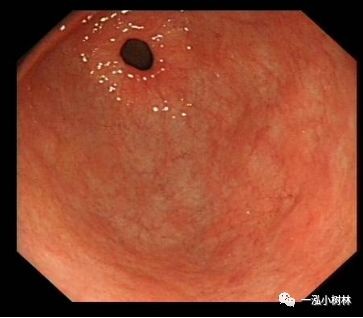

例3

女性,40岁,萎缩性胃炎+Hp感染